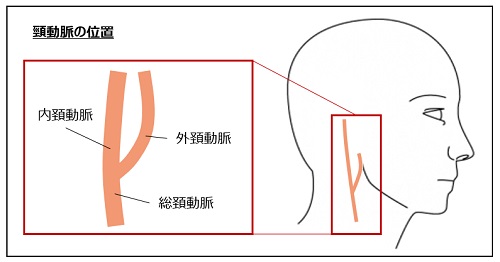

循環器検査 | 名古屋循環器科・内科 | 中村区名駅, 頸動脈エコーと動脈硬化検査 | 川崎市幸区の川崎中央クリニック,

頸動脈エコーと動脈硬化検査 | 川崎市幸区の川崎中央クリニック, 血管年齢 - 高津駅前はら内科ハートクリニック,

血管年齢 - 高津駅前はら内科ハートクリニック, 動脈硬化③ - 頚動脈超音波(頚部US)検査 - | 2020年 | コラム,

動脈硬化③ - 頚動脈超音波(頚部US)検査 - | 2020年 | コラム, 四谷三丁目・四谷・四ツ谷の内科・循環器内科・外科 | まがり,

四谷三丁目・四谷・四ツ谷の内科・循環器内科・外科 | まがり, 超音波検査(エコー検査) | あさひまちクリニック|旭川市旭町,